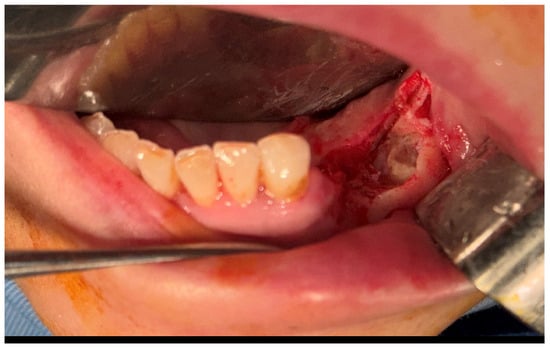

2.5. Third Surgical Intervention